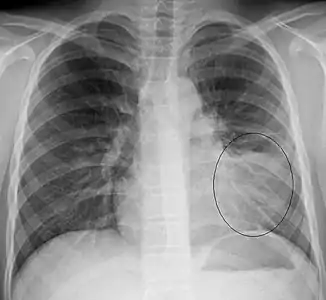

- AP CXR showing left lower lobe pneumonia associated with a small left sided pleural effusion

- Left upper lobe pneumonia with a small pleural effusion.